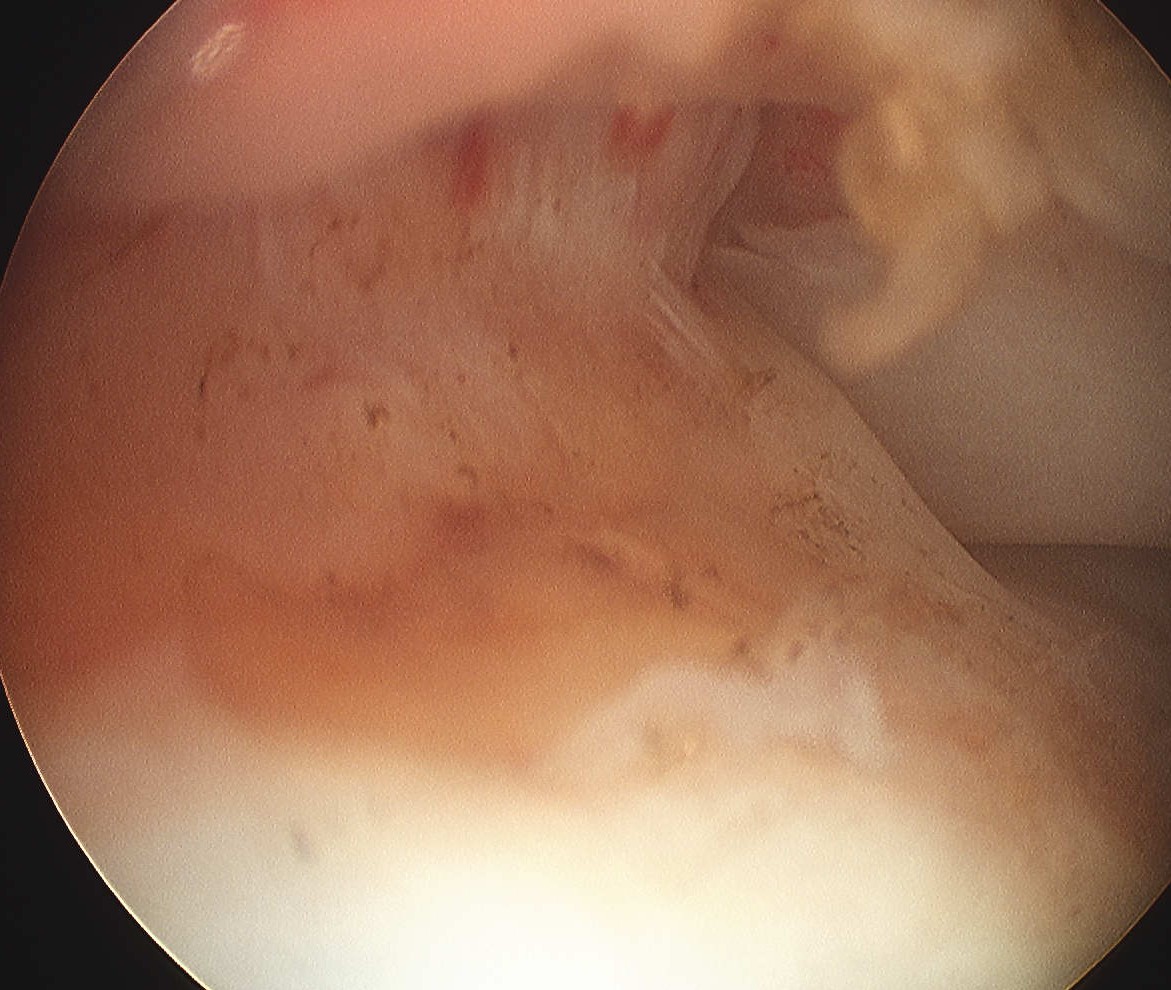

Bursal Sided

> 50% bursal sided tears with camer in subacromial space